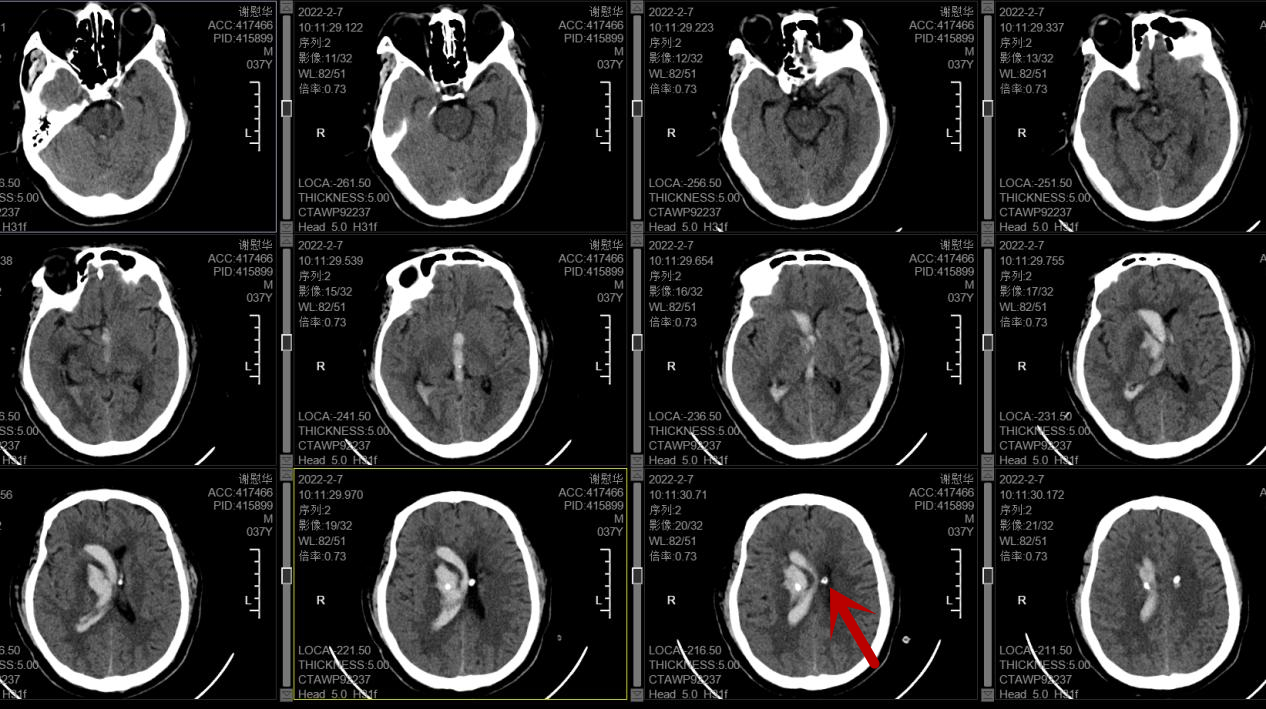

39岁的阿志(化名)体型较胖,2年多前发现有血压升高,平时偶然有头晕,但并没十分在意,未到正规医院进一步进行诊治,前段时间,阿志打牌时突感头晕、左侧手脚乏力,继而意识不清并瘫倒在地上,家属发现后立即将阿志送至我院急诊科,查头颅CT提示右侧基底节及脑室出血,量达26毫升,颅内出血量中等量多,但阿志此时血压明显增高,已意识不清,无法言语,病情危重,急诊医师立刻开通绿色通道收入神经外科。

术前头颅CT(红箭头所指为脑出血位置)

神经外科主任、主任医师王智勇查看患者病情后表示,此次脑内出血部位为高血压病常见的脑出血部位,与平时血压控制不好有非常大关系,患者可能在打牌期间出现激烈的情绪波动,导致血压波动大,从而引致血管破裂出血,目前患者已经意识不清,有手术指征,需急诊手术治疗。经过与家属的耐心沟通,同意采用三维定向置管的微创手术方案。